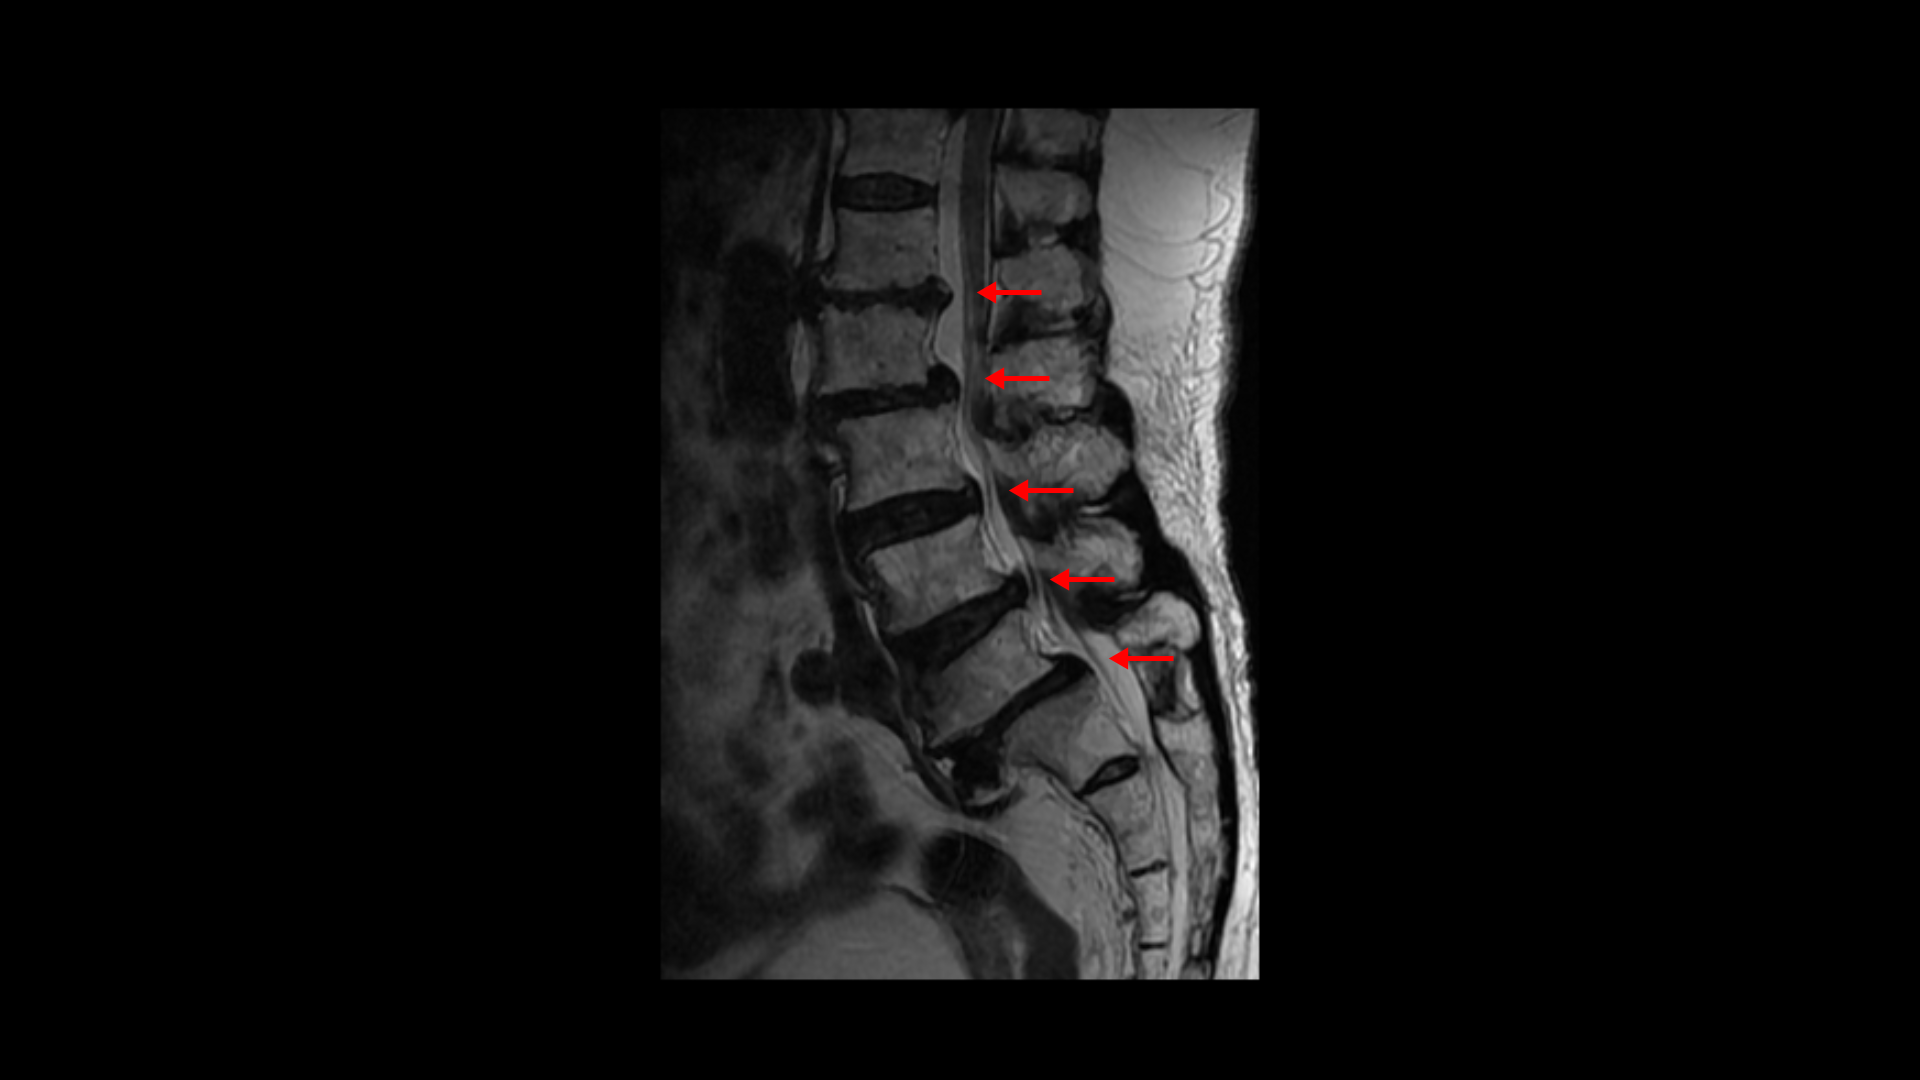

이분 MRI를 보면 보시다시피 허리의 5마디가 전부 퇴행이 진행되어 있습니다.

우선 전방전위가 2마디에 있고

여러 마디 2번 3번, 4번 5번에 척추관협착이 있고

2번 3번, 4번 5번, 오른쪽 신경가지가 빠져나가는 구멍들이 다섯 마디 전부가 다 오른쪽 좁아져 있습니다.

이분의 오른쪽 엉치와 다리가 저리고 아픈 원인은 이것 때문인 걸로 보입니다.

그런데 이분은 허리도 굽으셨는데 척추근육, 특히 허리를 세워주는 기립근을 mri에서 보면 허리 다섯 마디 전체에서 기립근의 근육이 지방으로 변해서 하얗게 보이는 지방화가 심합니다.

이렇게 근육이 지방으로 심하게 변하고 기능이 떨어지면 허리를 펴기가 어렵고 허리가 아플 수 밖에 없습니다. 여기 건강한 기립근과 비교해서 보면 그 차이를 금방 알 수가 있습니다. 기립근 크기도 차이가 크고 하얗게 지방으로 변해버린 부분을 잘 보실 수 있습니다.